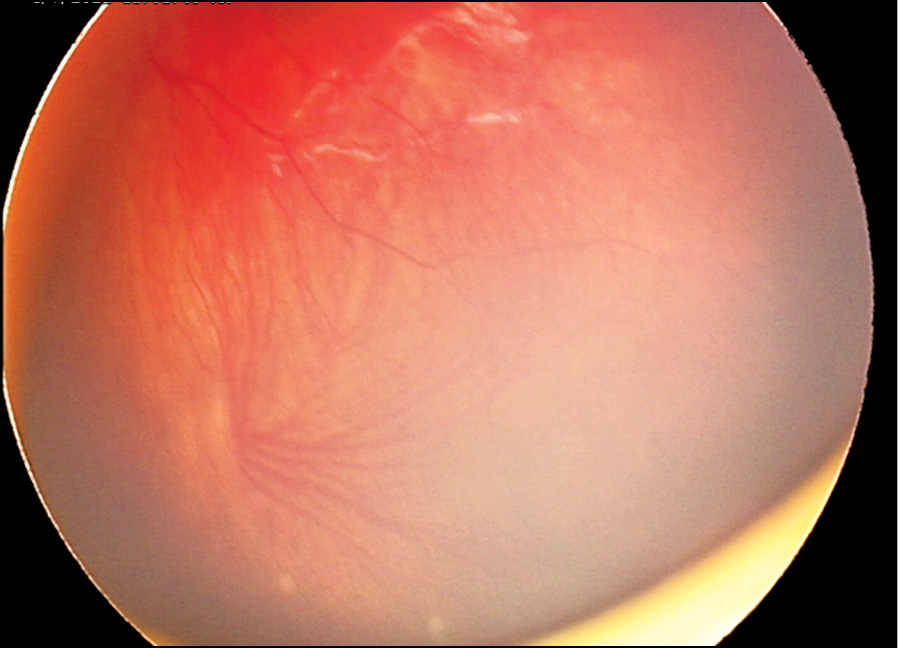

Клинический случай 1. Недоношенный мальчик, рождённый на 29-й недели гестации в результате экстракорпорального оплодотворения, из двойни, с массой тела 1350 г. Находился на лечении и выхаживании в СПб ГБУЗ «ДГБ №1» (в 2019 г. переименована в СПБ ГБУЗ «Детский городской многопрофильный клинический специализированный центр высоких медицинских технологий»). Первичный офтальмологический скрининг с помощью педиатрической ретинальной камеры «RetCam3» (США) проведён при достижении ребёнком 31-й недели постконцептуального возраста (ПКВ). При этом выявлены признаки незавершённости васкуляризации сетчатки на крайней периферии обоих глаз. В процессе регулярного мониторинга за состоянием глазного дна была диагностирована активная РН 2-й стадии с локализацией в зоне II сетчатки (рис. 1). К 36-й неделе ПКВ прогрессирование заболевания достигло порога (стадия 3, «плюс-болезнь»), что потребовало лазерного хирургического лечения. Для проведения лазерной коагуляции аваскулярных зон сетчатки использовали диодный лазер с длиной волны 532 нм (Iridex, США) и транспупиллярный доступ. После выписки из стационара было продолжено динамическое наблюдение офтальмологом в кабинете катамнеза амбулаторно-поликлинического отделения данного учреждения, где у пациента в 38 недель постконцептуального возраста зарегистрирован и документирован индуцированный регресс РН (рис. 2). Следующий осмотр состоялся через 2 недели (ПКВ — 40 недель), во время которого был обнаружен очаг опухоли в макулярной области сетчатки (рис. 3). Так как результаты всех обследований глазного дна с помощью RetCam регистрировались и архивировались в базе данных пациента, ретроспективный анализ ранее выполненного изображения показал наличие точечного очага опухоли, расположенного в центре макулы левого глаза (рис. 2), который корректно не интерпретировали, сосредоточив внимание на клинической картине РН. Несмотря на сверхмалый размер очага данный случай РБ относится к группе В исходя из его локализации.

Рис. 1. Активная РН: стадия 2, зона II. РН — ретинопатия недоношенных.

Fig. 1. Active ROP: stage 2, zone II. ROP — Retinopathy of Prematurity.